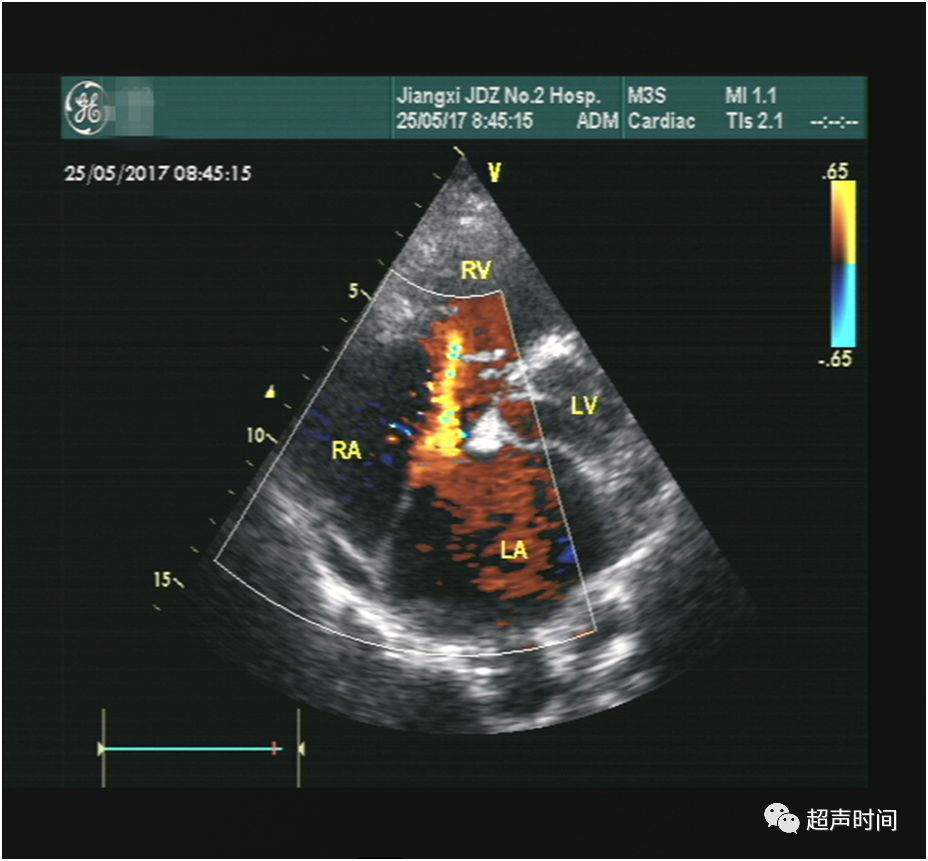

超声所见:M 型超声显示二尖瓣呈平台样改变,前后叶同向运动,回声增厚增强,开放受限,开放幅度约 0.94 cm,描迹瓣口面积约 1.8 cm²(图 1 和 2)。频谱多普勒示二尖瓣前向血流增快,PHT 估测瓣口面积约 1.8 cm²(图 3)。CDFI 示收缩期三尖瓣可见轻中度反流,据此估测的肺动脉收缩压正常(图 4)。房间隔中部见约 1.2 cm 连续中断,可见连续性左向右分流血流信号,峰速115 cm/s (图 5~图 7)。

图 3 频谱多普勒示二尖瓣前向血流流速增快,据 PHT 估测瓣口面积

图 6 CDFI 显示房间隔缺损处的左向右分流